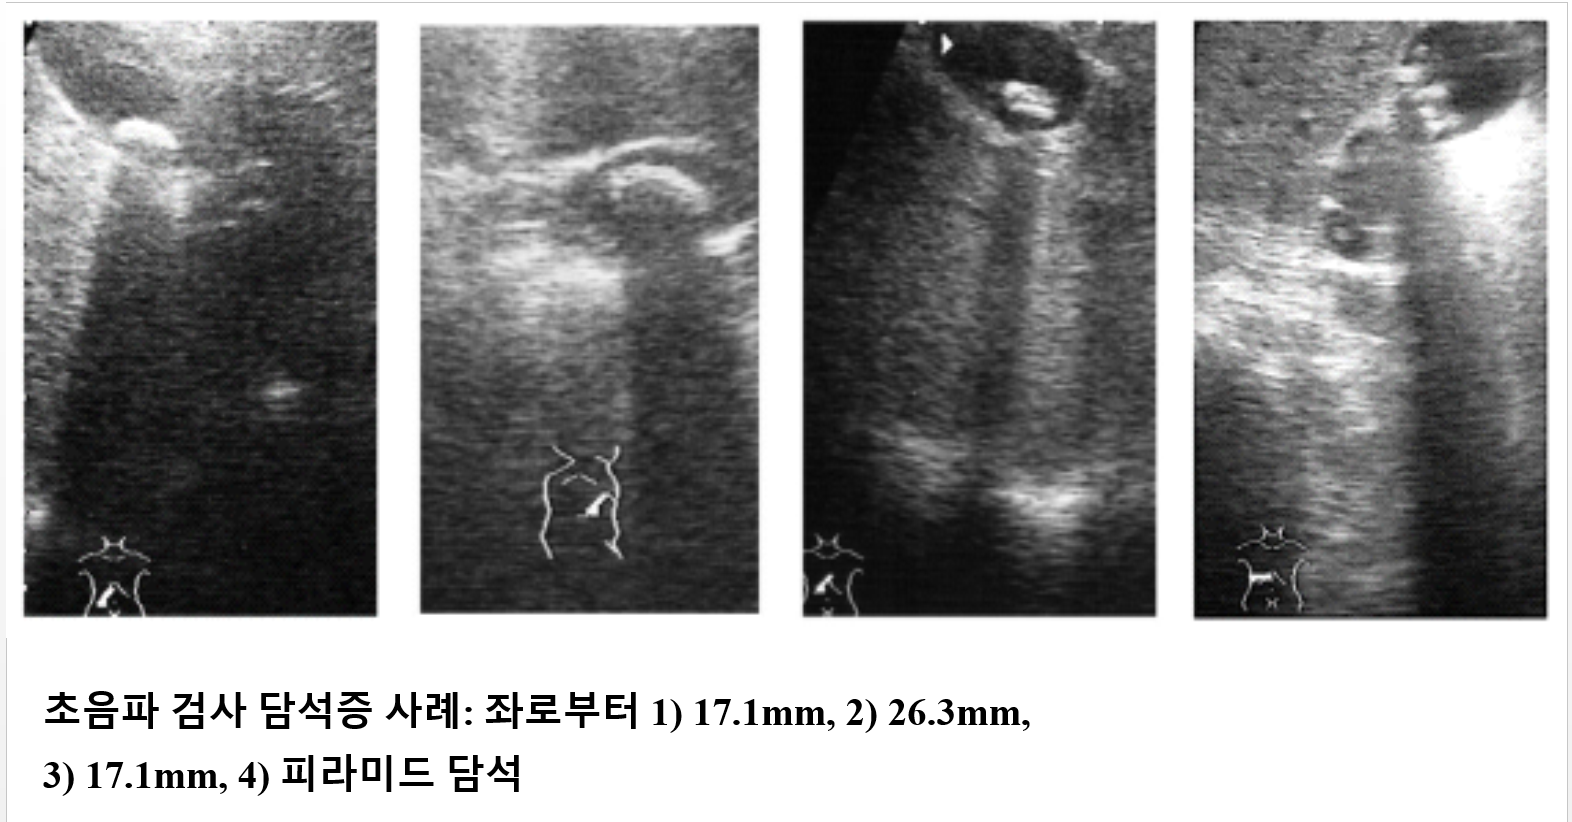

초음파검사는 실시간 초음파기기 SonoAce 4800HD(Medison Co.,Ltd.)로 3.5MHz Curved array(Convex) probe를 사용했으며, 주사면에 초음파 젤을 충분히 바른 후에 초음파 탐촉자와 주사면이 수직이 된 상태에서 측정했다.

담석의 초음파 검사 소견은 후방음향음영(posterior acoustic shadowing)을 갖는 강한 반사체, 환자의 체위 변경에 따른 반사체의 이동을 중요 기준으로 삼았으며, 환자로 하여금 바로 누운 자세와 좌측 측와위 자세를 취하게 하고, 우 늑골궁하 우늑간 간하연 스캔을 통해 담낭을 관찰했다.

이와 함께 감별진단 및 주의점으로는 담낭용종(Gallbladder Polyp)은 음향음영을 동반하지 않고 체위 변환에도 불구하고 용종이 이동하지 않고 음향음영을 동반하지 않는 것이 특징이다.

이에 담낭용종은 크기에 따라 5mm이하, 5~10mm, 10mm이상의 3부류로 나누어 경과를 관찰하는 것이 좋으며, 10mm이상의 비교적 큰 용종은 담낭암 등 악성종양의 존재유무를 정밀 진단할 필요가 있다.